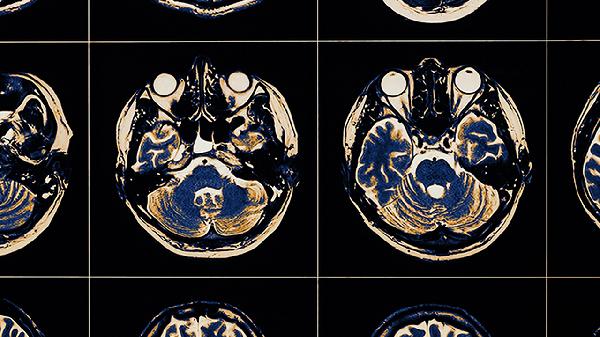

缺血缺氧性脑病的治愈可能性取决于病情的严重程度和治疗的及时性。轻度患者通过早期干预可能恢复较好,而重度患者可能遗留永久性损伤。治疗的核心在于改善脑供氧、促进神经修复、控制并发症。